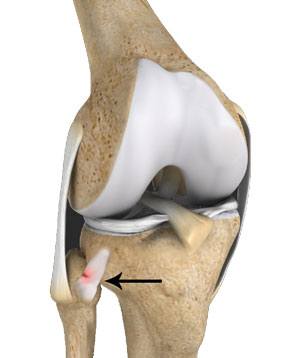

- There are acute and chronic causes of instability with four patterns: anterolateral dislocation, posteromedial dislocation, superior dislocation, and atraumatic subluxation. Anterolateral dislocation is the most common and is caused by a violent twisting of the flexed knee with the foot inverted and plantarflexed. The lateral collateral ligament and biceps femoris tendons relax when the knee is flexed to at least 30 degrees, which allows the fibula to move anteriorly. This decreases the joint’s stability. Inversion and plantarflexion of the foot pulls on the peroneal muscles, which are attached to the fibula and foot, and causes the fibula to dislocate anteriorly tearing the posterior tibiofibular ligaments.